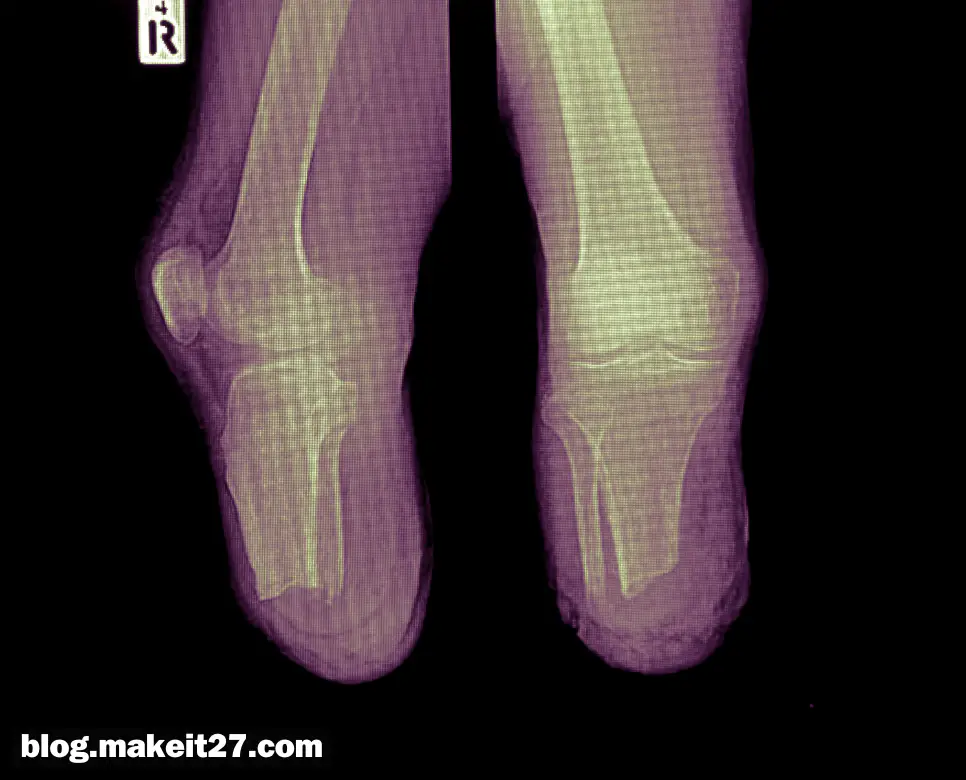

BKA는 의학 용어로 ‘Below Knee Amputation’의 약자이며, 한국어로는 ‘무릎 아래 절단술’ 또는 ‘하퇴 절단술’을 의미합니다. 이는 발목과 무릎 사이의 하퇴부를 절단하는 수술 절차를 말합니다. BKA는 주로 심각한 외상, 감염, 혈관 질환 또는 종양으로 인해 다리의 일부를 구할 수 없을 때 시행됩니다.

이 수술은 환자의 생명을 구하고 삶의 질을 개선하는 데 중요한 역할을 합니다. 예를 들어, 당뇨병성 족부 궤양이 심각하게 진행되어 다른 치료 방법으로는 해결할 수 없는 경우 BKA가 고려될 수 있습니다.